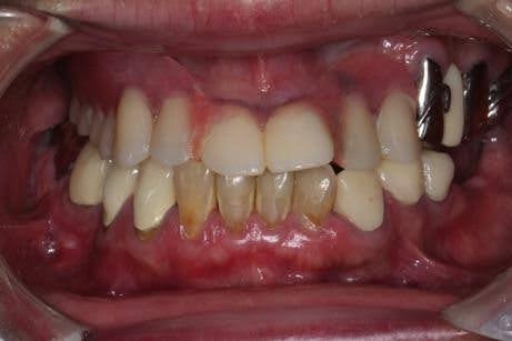

削らず、美しく整える “矯正 × セラミック治療” の治療選択肢

「歯をあまり削りたくない」「でも見た目も整えたい」そんな方のために、矯正とセラミック治療を組み合わせた方法です。先に歯並びを整えることで、必要以上に削らず、自然でキレイな見た目に仕上げることができます。噛み合わせも良くなるため、治療も長持ちしやすいのが特徴です。

このような方に、当院の矯正×セラミック治療のハイブリッド治療は特におすすめです。